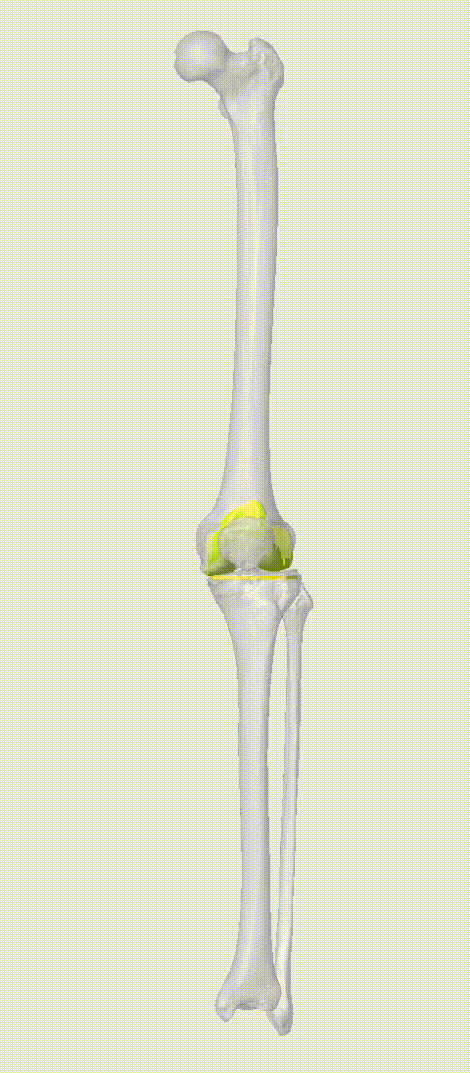

根据患者的二维影像学数据,对患者骨骼解剖结构进行三维重建,清晰展示患者骨骼病变情况。根据术式及手术目标,AI软件自动测量多项关键数据,根据实际数据自动完成假体选型、假体摆放、优化假体对位关系、截骨量测算、术中关键数据推算等工作,最终形成可视化术前规划报告。

术前三维重建及假体位置模拟

文益民主任秉持着负责的态度和精益求精的原则,全方位、多角度观察了患者的骨骼解剖结构,充分了解了患者病变情况,并最终确定了手术方案细节。AI软件一键生成PSI导板数据、生成导板外观,并发送给打印机进行导板制备。